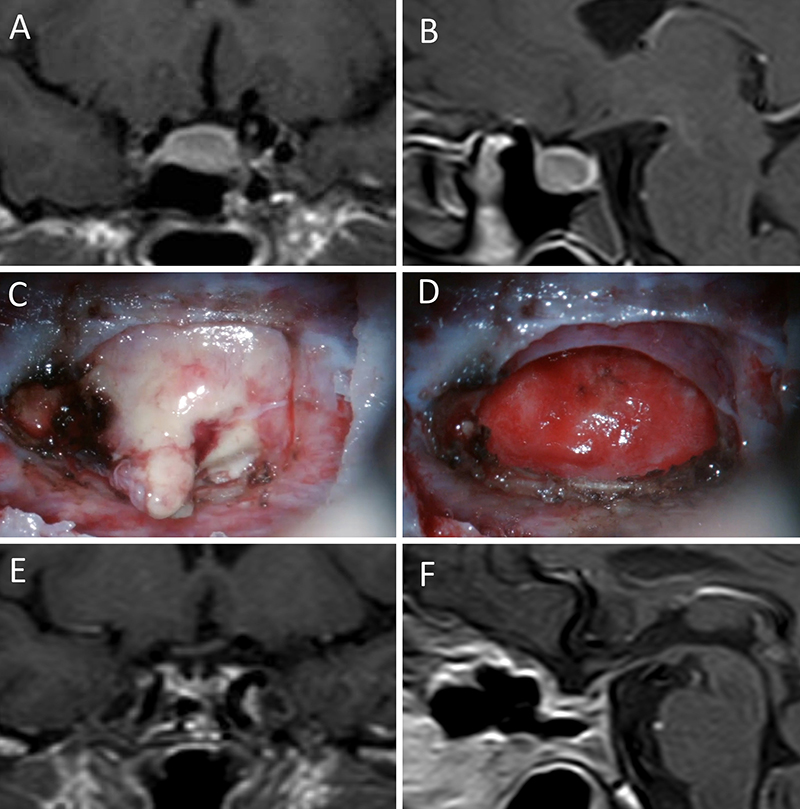

Figura 1: Macroadenoma no funcionante en mujer de 65 año

s. Se decidió la cirugía tras evidenciarse crecimiento en los controles. Evolucionó favorablemente desde el punto de vista clínico-radiológico. A-B: RM preoperatoria; C-D: intraoperatorio; E-F: RM postoperatoria.